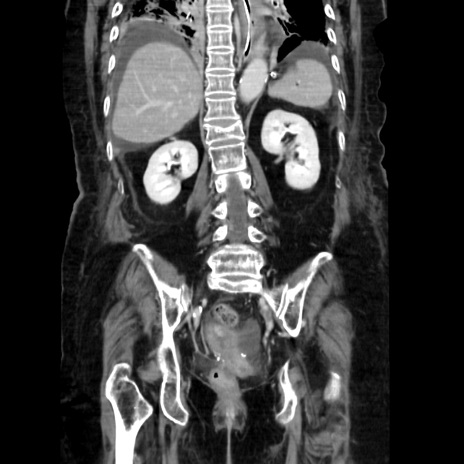

症例40(冠状断像)

【症例】90歳代女性

【主訴】腹痛・嘔吐

【身体所見】腹部:中央に激痛あり、圧痛あり、反跳痛不明

【データ】WBC 17100、CRP 18.82

冠状断像